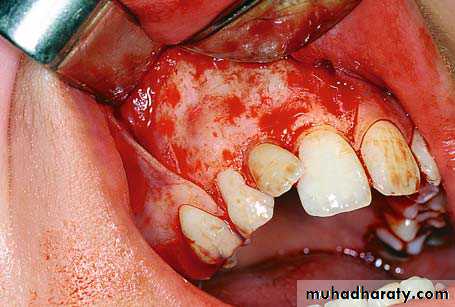

Clinical photograph of the labial area where the right canine is localized labially

right canineSurgical procedure for removal of right impacted canine. A trapezoidal incision is created buccally. It is desirable to make an intersulcular incision extending to at least one to two teeth in each direction from the area of interest

Reflection of the mucoperiosteal flap

Note: A common error is to develop a small flap and extend it conservatively. This approach, although reasonable in theory, in practice often leads to tearing of the flap and/or inadequate exposure, ultimately resulting in a poor outcome. A well planned and properly retracted large flap generally heals as well, if not better, than a traumatized small flap.A round bur is used to remove the bone covering the crown of the tooth